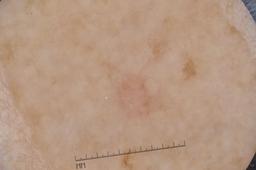

MSK-4

- Name: MSK-4

Description:

Images found based on a search for patients with a personal history, clinical diagnosis, or differential diagnosis of melanoma. All diagnoses confirmed by histopathology.